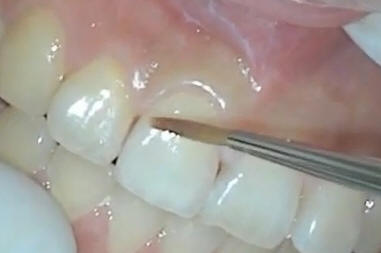

Retirar el provisorio

desde palatino con un baja puente |

Retirar

remanente de cemento en el borde cabo superficial de la

restauración |

Probar el el ajuste del

biscocho, debe llegar hasta el borde cabo de la restauración

y debe tener estabilidad buco-palatina Chequear

oclusión con papel de articular . En este caso no se tomo

registro intermaxilar y antagonista dado que el paciente

presenta una buena alineación tridimensional. El técnico al

lograr la morfología de la pieza dental homologa, no fueron

necesarios los registros intermaxilares. Esto solo lo

hacemos cuando reponemos una sola pieza dental en un arco

con una buena alineación tridimensional; en caso de ser dos

o más, los registros intermaxilares y modelo antagonista son

expresamente necesarios. |

| No debe haber enganche

cuando se pasa una sonda |